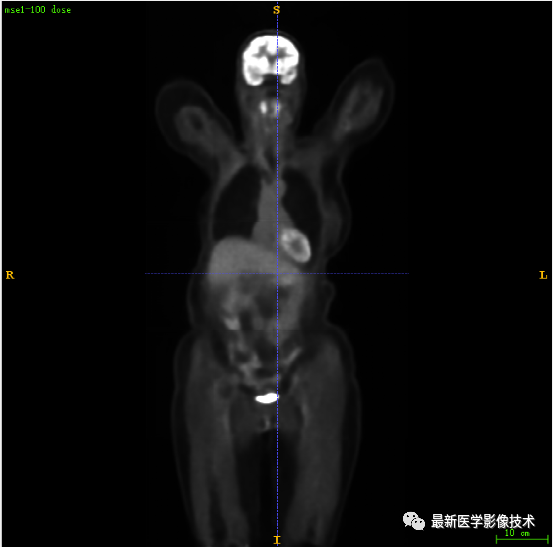

7.4、低剂量20重建结果

第一张是低剂量20的PET图像,第二张是full剂量PET图像,第三张是网络重建的PET图像。